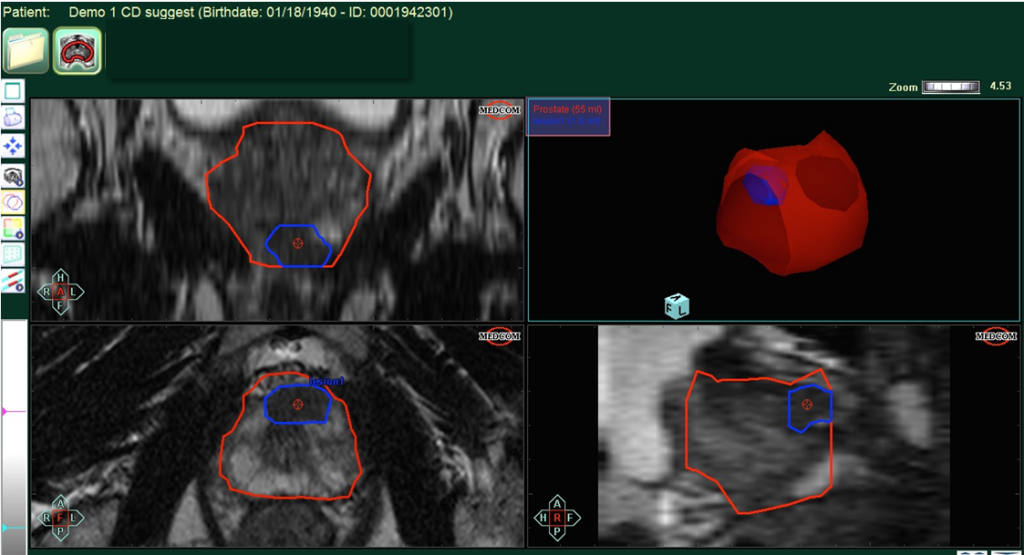

Εικόνα 1: Σχεδιασμός του προστάτη (κόκκινο σχεδιάγραμμα) και σχεδιασμός της βλάβης (μπλε σχεδιάγραμμα).Με τον τρόπο αυτό σχεδιάζεται η βλάβη και ο ουρολόγος εν συνεχεία με την Fusion βιοψία προστάτη λαμβάνει στοχευμένες βιοψίες (Εικόνα από την συλλογή της Medcom).

-Οι ουρολόγοι της ομάδας Advanced Urology ( Δρ.Ιωάννης Λεωτσάκος & Δρ.Ι.Καταφυγιώτης) τοποθετούν το CD της μαγνητικής στο ειδικό μηχάνημα με το κατάλληλο λογισμικό(BiopSee-Medcom) και κάνουν τον σχεδιασμό του προστάτη και των βλαβών.(Βλ.Εικόνες 5 & 6)

Εικόνα 6: Πολυπαραμετρική μαγνητική τομογραφία προστάτη με σχεδιασμό του προστάτη (Κόκκινο πλαίσιο) και ξεχωριστό σχεδιασμό της βλάβης (Μπλε Πλαίσιο).Ο προστάτης και η βλάβη αρχικά σχεδιάζονται και είναι ιδιαίτερα σημαντικό ο ουρολόγος να έχει την κατάλληλη εκπαίδευση στην ερμηνεία των εικόνων της μαγνητικής.